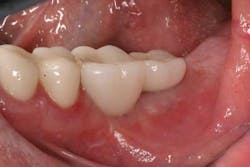

Case study A 58-year-old male with a noncontributory medical history presented to a private practice for a complete rehabilitation of his dentition due to years of bruxism and parafunction. (Fig. 1) After surgical and restorative consultations, a treatment plan was fabricated. The treatment plan included restoring his lost vertical dimension, restoring his natural dentition with porcelain-fused-to-metal full-coverage crowns, and replacing his lost posterior teeth with dental implants. After his vertical dimension was restored with an acrylic bite plate to a position harmonious with TMJ function, crown-lengthening surgery was performed. (Fig. 2)Fig. 2 Six weeks after, the teeth were temporized to develop soft tissue margins/interdental papillae. (Figs. 3 and 3a) The patient was kept in temporaries for three months, during which time an implant was placed in site No. 19. Both the natural dentition and the implant were completed at the same time, three months after implant placement. (Fig. 4) Because of the patient’s occlusal issues, the implant was screw-retained, and the patient was given a maxillary night guard. Three weeks after insertion, the patient presented with a loose abutment screw. The dentist tightened the screw and sent the patient home. This cycle was repeated two more times until the patient presented again with a loose crown, but this time, a fracture implant screw. The dentist attempted to remove the screw with a Cavitron and drilling the implant screw out to release preload, but to no avail. The case was then referred to my office for implant removal.